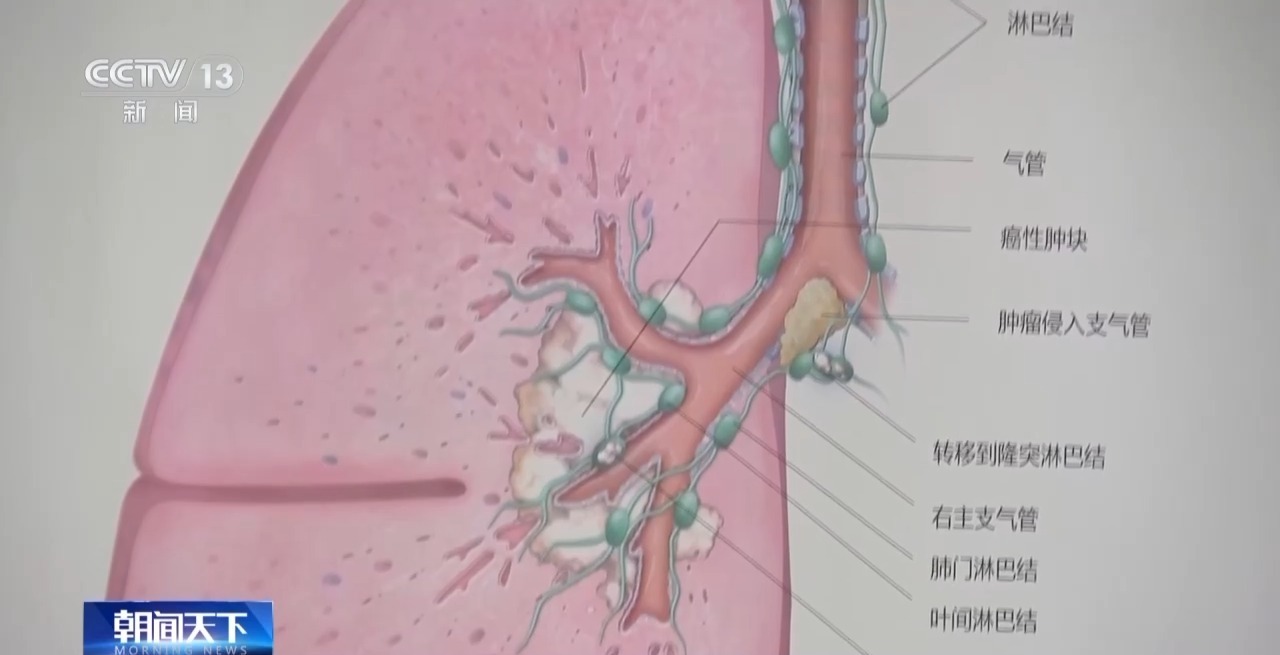

非高危东谈主群不必每年进行CT筛查

我国当今实验社区CT筛查肺癌,北京一些区域已将肺癌筛查纳入慢性病处置,障翳东谈主群超百万。大师同期强调,低剂量螺旋CT有放射,非高危东谈主群无须每年进行CT筛查,即就是发现肺部有磨玻璃样结节,也切莫过度弥留,按需就诊即可。

北京大学肿瘤病院胸外一科主任 陈克能:对那些非高危的东谈主群,即就是低剂量螺旋CT看见了小结节,咱们也要分如下的情况,如果是一个纯磨玻璃样结节,浮浅说莫得实性因素,就不要过度惊愕;如果结节位置不在胸膜下,又不在叶间裂,这些大可不必弥留,莫得必要每一年作念一次CT。

快播小电影大师暗示,对大无数筛查发现的磨玻璃样小结节要严慎解读,它孕育得相配渐渐,不错给它一定的平展期进行不雅察,不提倡过度养息。

北京大学肿瘤病院胸外一科主任 陈克能:全球把这种磨玻璃样小结节的肺癌,混同于正本传统的肺癌,这是要不得的。磨玻璃样结节的肺癌跟传统的肺癌,其实它的转归预后不是一趟事,浮浅说它是一个相配懒惰的“懒”癌。

跟着我国医学高出,肺癌患者的养息有显然冲突,磨玻璃样结节的肺癌,5~10年的生涯率接近百分之百,实性肿块一期肺癌的5年生涯率约为70%~80%。